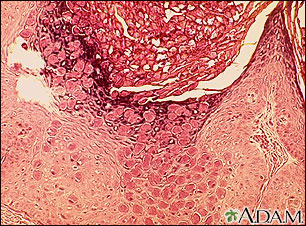

Molluscum contagiosum is a viral skin infection that causes raised, pearl-like papules or nodules on the skin.

The infection on the skin begins as a small, painless papule, or bump. It may become raised to a pearly, flesh-colored nodule. The papule often has a dimple in the center. Scratching or other irritation causes the virus to spread in a line or in groups, called crops.

The papules are about 0.08 to 0.20 inches (in) or 2 to 5 millimeters (mm) wide. Usually, there is no inflammation (swelling and redness) and no redness unless they have been irritated by rubbing or scratching.

If needed, the diagnosis can be confirmed by removing one of the lesions to check for the virus under a microscope.